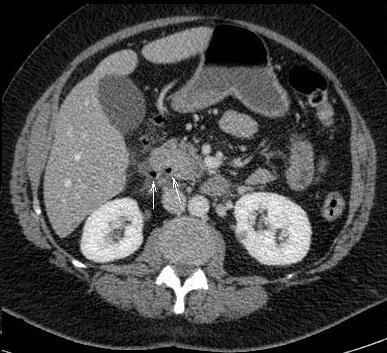

Perforation du tube digestif

. Image TDM en coupe axiale se donne la presence de

air libre a l' espace superieur de l'abdomen . Le

diagnostic est vers estomac et duodenum

par la presence des petites bulbes d'air intra

parietale . |

Diagnostic d'ulcere perfore sur la

TDM se verifie quand : la presence de

pneumoperitoine , epaissisement irregulie de la

paroi duodenale ou gastrique , bulbe d'air intra

parietale , infiltration graisseuse mesentrique et

epanchement liquidienne intra peritoneal |

La presence des petits bulbe

d'air intra parietale posterieure : ulcere de la

face posterieure perfore |

Ulcere gastro duodenal perfore : Image

TDM en coupe axiale |